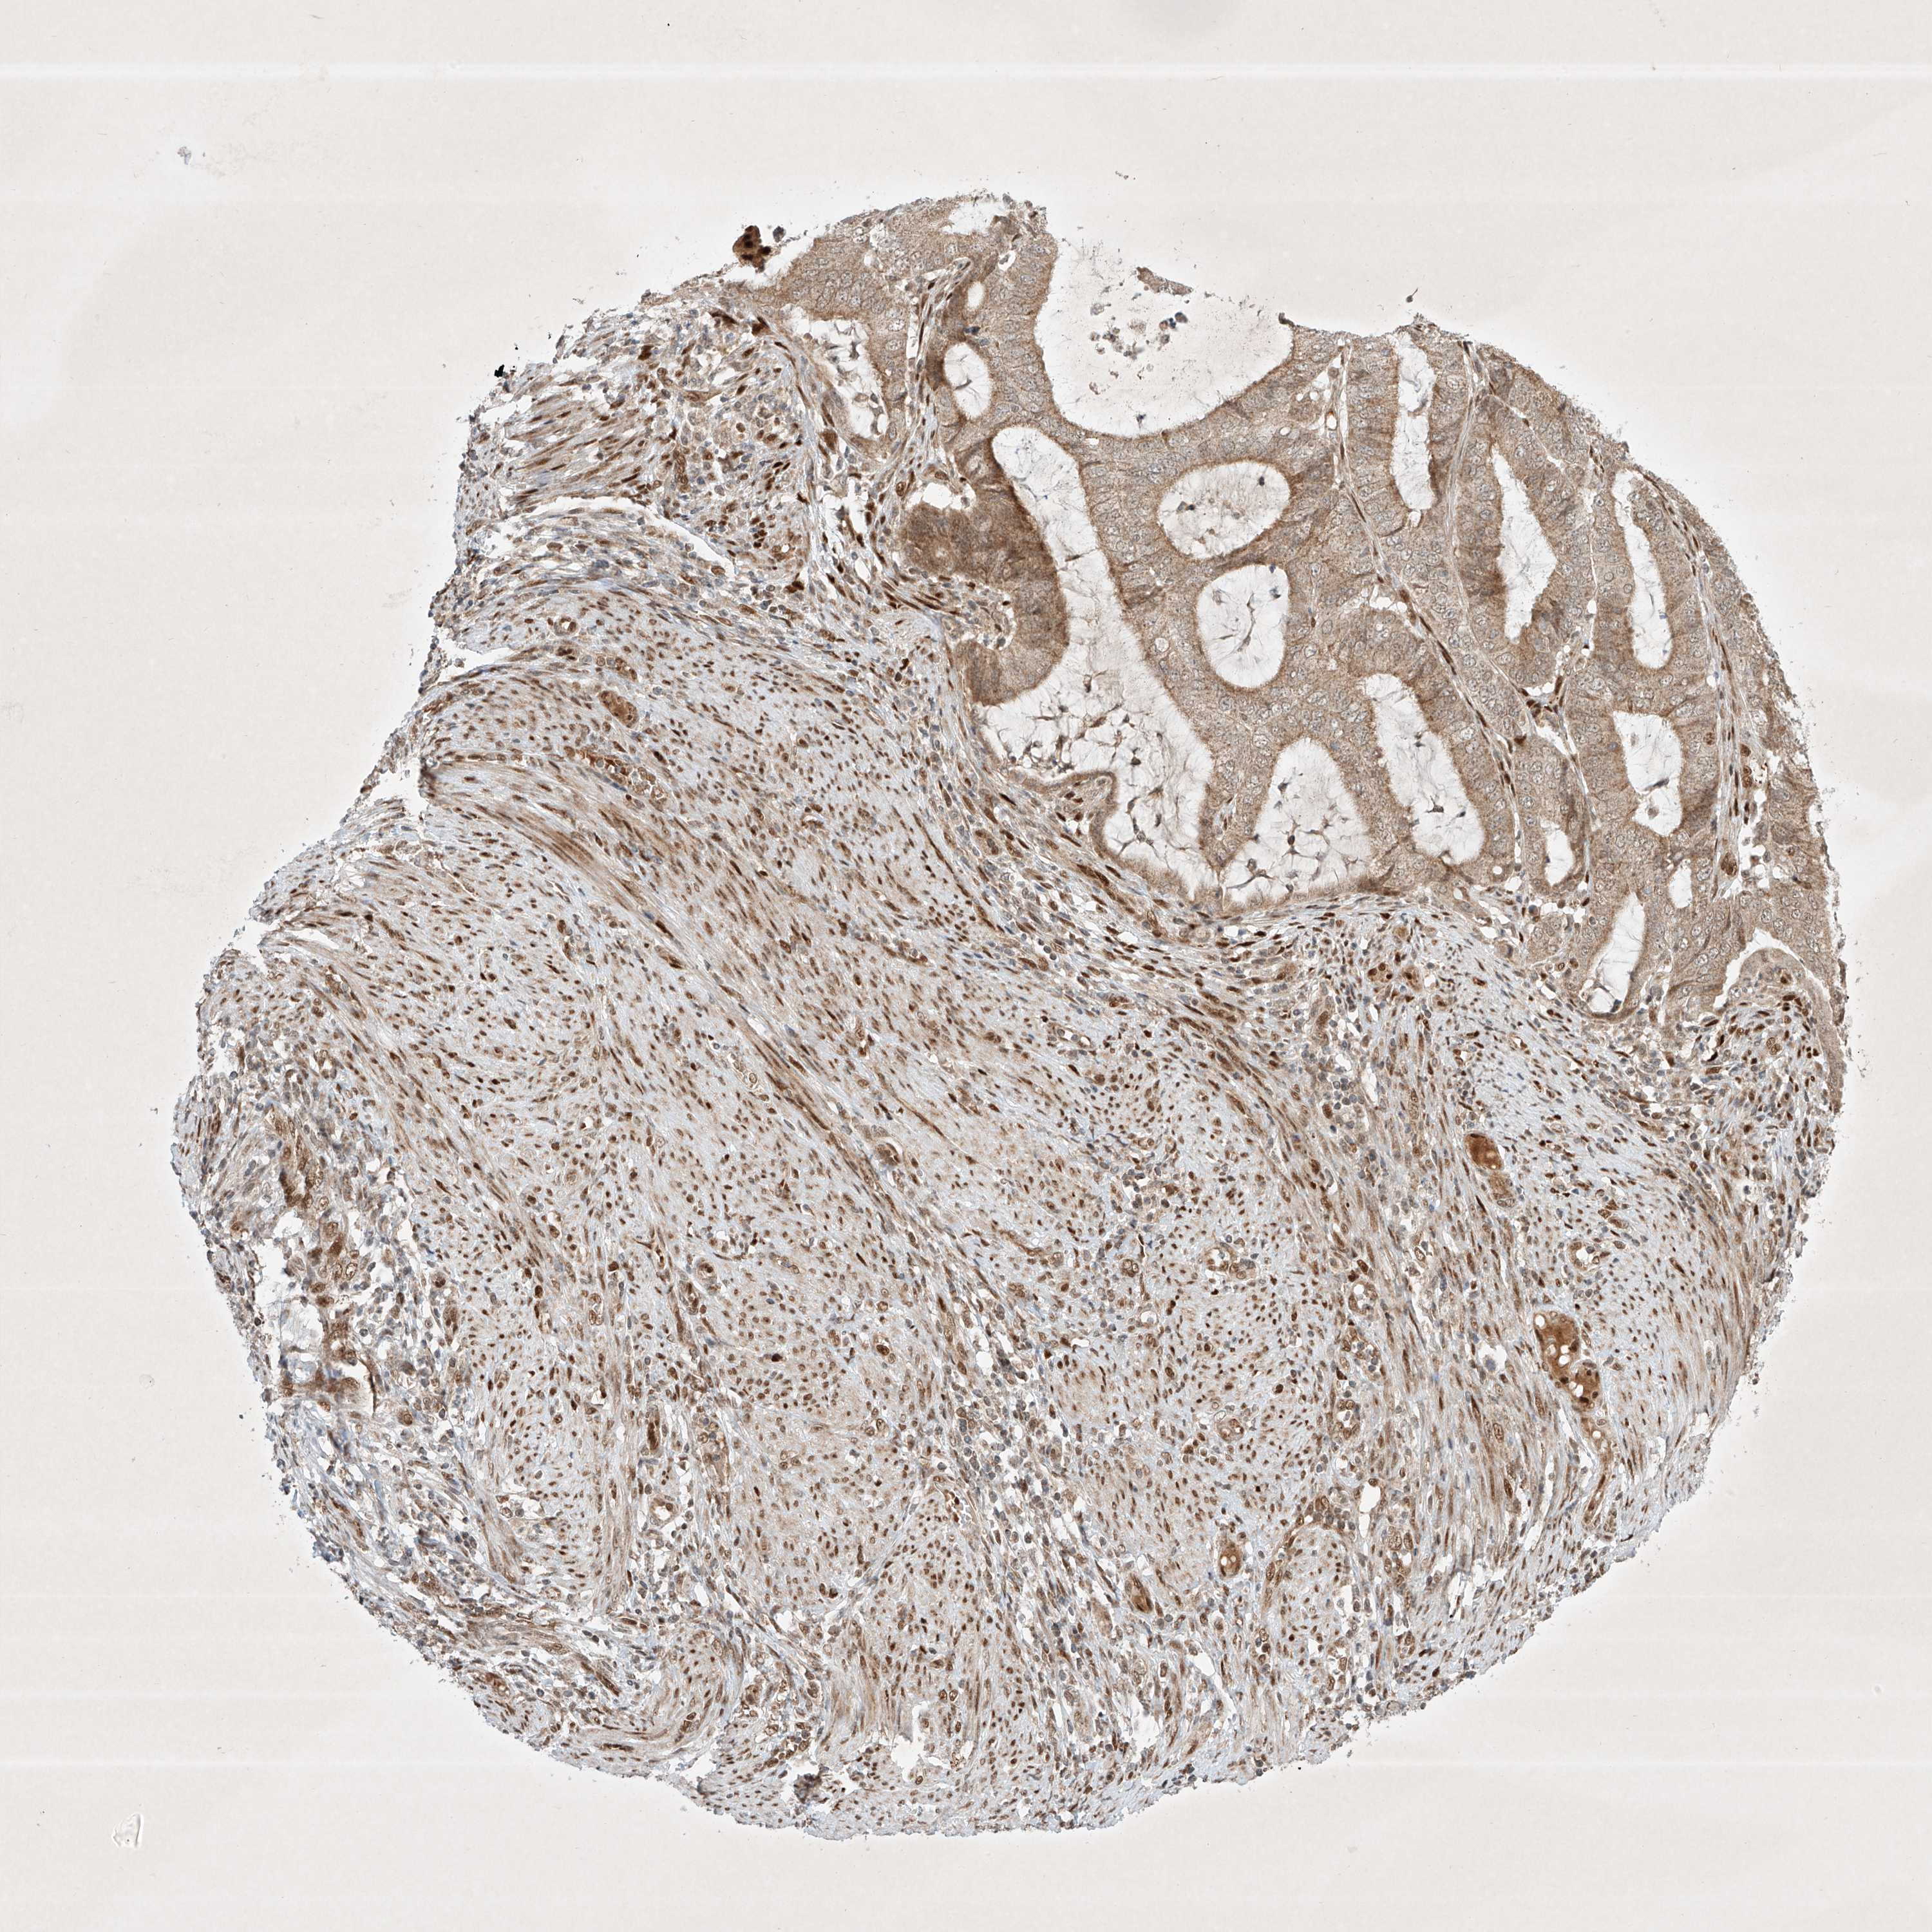

ENDOMETRIAL CANCER - Protein expressioni

A mouse-over function shows sample information and annotation data. Click on an image to view it in a full screen mode. Samples can be filtered based on level of antibody staining by selecting one or several of the following categories: high, medium, low and not detected. The assay and annotation is described here.

Note that samples used for immunohistochemistry by the Human Protein Atlas do not correspond to samples in the TCGA dataset.

Antibody stainingi

Antibody staining in the annotated cell types in the current human tissue is reported as not detected, low, medium, or high, based on conventional immunohistochemistry profiling in selected tissues. This score is based on the combination of the staining intensity and fraction of stained cells.

Each image is clickable and will lead to virtual microscopy that enables deeper exploration of all samples and also displays staining intensity scores, fraction scores and subcellular localization as well as patient and tissue information for each sample.

Antibody HPA031689

Staining

High

Medium

Low

Not detected

Intensity

Strong

Moderate

Weak

Negative

Quantity

>75%

75%-25%

<25%

None

Location

Nuclear

Cytoplasmic/membranous

Cytoplasmic/membranous,nuclear

Adenocarcinoma, NOS

Adenocarcinoma, metastatic, NOS